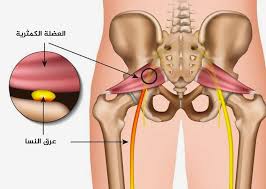

عرق النسا للرجال هو حالة صحية ناتجة عن ضغط أو تهيّج في العصب الوركي، وهو أطول وأكبر عصب في الجسم، يمتد من أسفل الظهر مرورًا بالأرداف والفخذين وصولًا إلى أسفل الساقين. وعندما يتعرض هذا العصب للضغط، يبدأ الألم في أسفل الظهر ويشعّ نزولًا إلى الساق، وقد يكون الألم مصحوبًا بوخز أو تنميل أو ضعف عضلي في الرجل المصابة.

يحدث عرق النسا للرجال غالبًا نتيجة انزلاق غضروفي في الفقرات القطنية، وهو ما يؤدي إلى ضغط مباشر على العصب الوركي. كما يمكن أن تنجم الإصابة عن الجلوس لفترات طويلة، أو رفع أشياء ثقيلة بطريقة خاطئة، أو بسبب تضيّق العمود الفقري مع التقدم في العمر. وتُعد المهن التي تتطلب مجهودًا بدنيًا أو قيادة لفترات طويلة من العوامل المساهمة أيضًا في تطور عرق النسا للرجال.

- تمارين الإطالة (Stretching): مثل تمديد العضلة الكمثرية وتمارين أوتار الركبة، لتقليل الضغط على العصب الوركي.